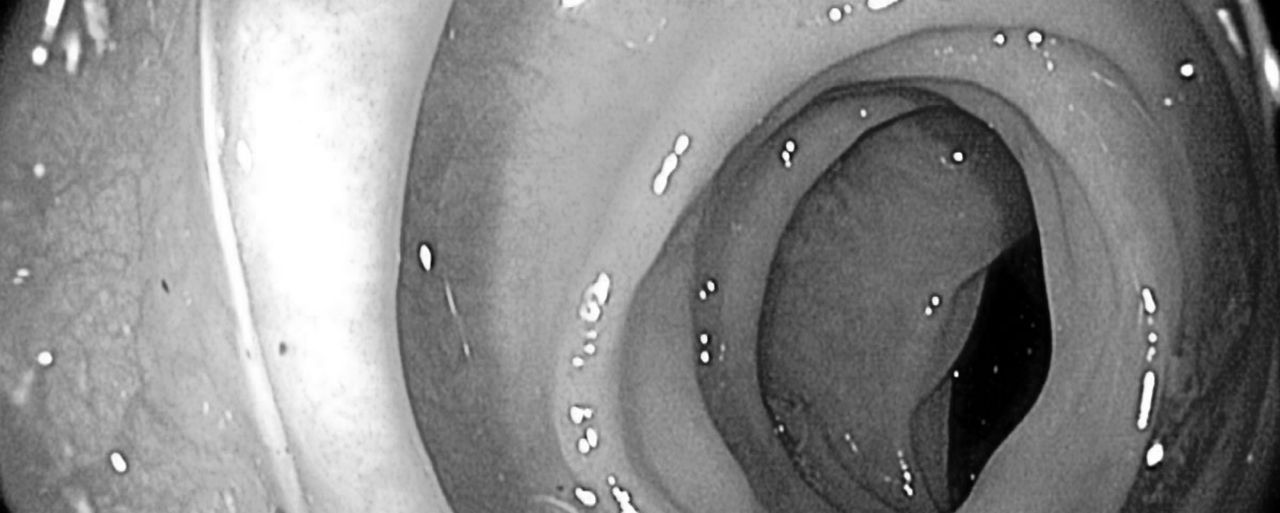

Capsule endoscopy

Non-invasive deep learning solution for small bowel mucosa evaluation.

Detect and differentiate endoscopic lesions with groundbreaking sensitivity and specificity. Accurately stratify the hemorrhagic potential of lesions. The aim is simple: ensure a better patient outcome by gaining diagnostic efficiency while sparing precious time. Seeing deeper, diagnosing more, treating better.

- Accurate detection and differentiation of lesions in capsule endoscopy exams.

- Precise automatic stratification of the hemorrhagic potential of lesions using a validated scale.

- Invaluable AI tool for obscure gastrointestinal bleeding.

- Increased diagnostic accuracy in small bowel diseases (Celiac Disease, Crohn's Disease, among others).

CAPSULE ENDOSCOPY

Detect and differentiate endoscopic lesions with groundbreaking sensitivity and specificity. Accurate stratification of the hemorrhagic potential of a wide range of lesions.